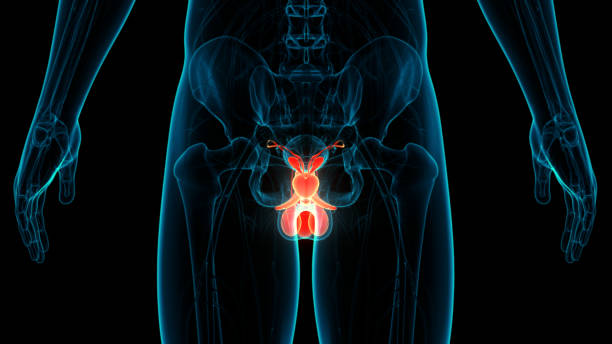

남성 생식기의 요로계와 직접적 연관이 있는 전립선은 사과 모양으로 배꼽 아래쪽에 위치해 있으며 상당히 중요한 역할을 하고 있습니다. 전립선은 사정을 조절하고, 정자의 움직임을 돕는 전립선 분비액을 만들어냅니다. 이 분비액은 정자의 영양 공급과 이동에 필수적인 성분을 포함하고 있습니다. 또한, 전립선은 방광을 둘러싸고 있는 방광 경화근과 골반 바닥 근육에 대한 지지 구조 역할을 할 수 있어 상당히 중요하나 전립선에도 암이 발병될 수 있어 초기에 원활한 대응을 해야만 합니다. 그럼 이번 시간에는 전립선암 초기증상에 대해 자세히 정리해보겠습니다.